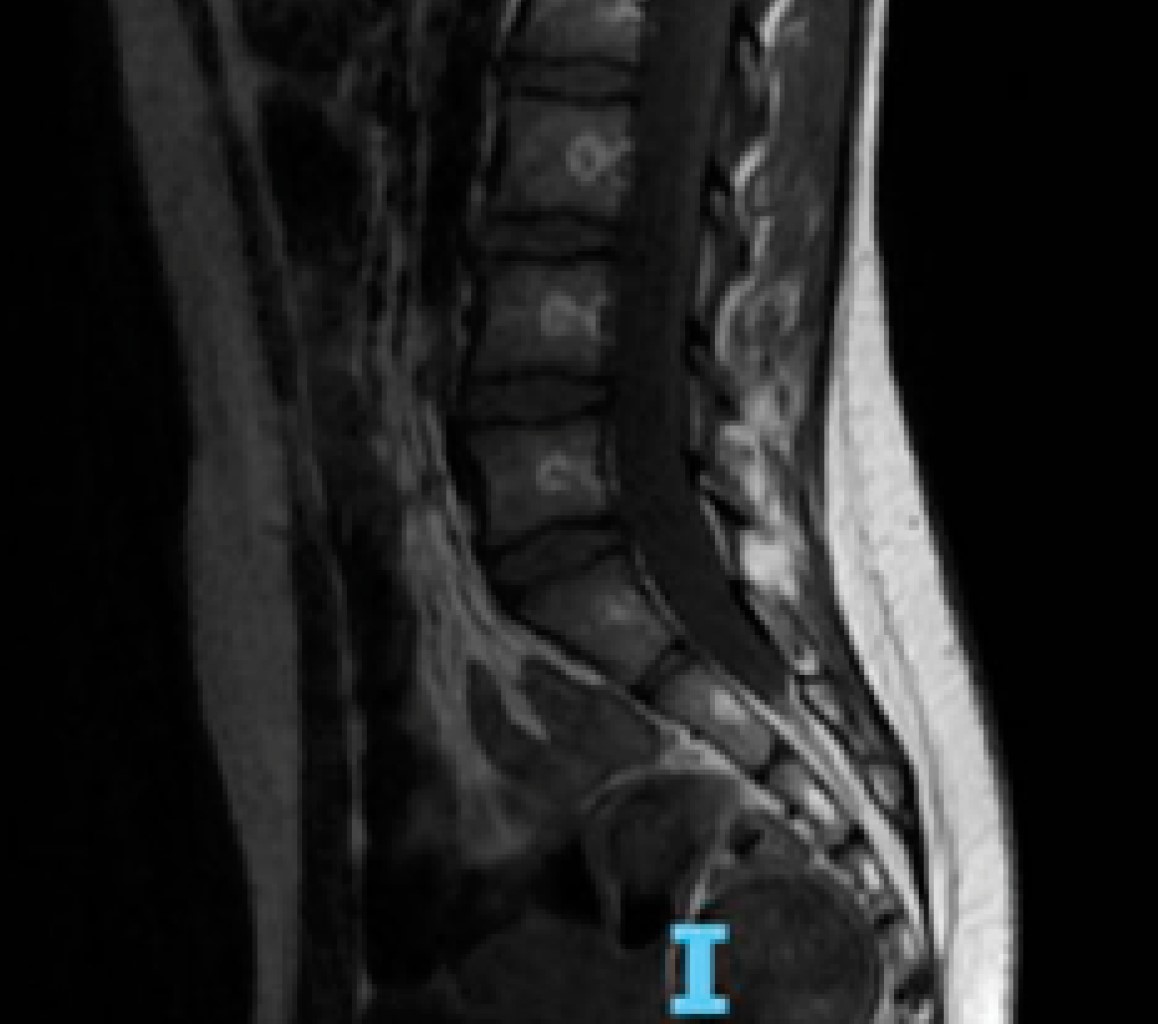

Inicia padecimiento en agosto de 2022 posterior a caída de tres escalones, con debilidad en extremidades inferiores, acude al médico quien integra diagnóstico de infección respiratoria aguda y la envía a casa con tratamiento sintomático, con mayor progresión de la debilidad a miembros superiores. En septiembre, acude a consulta para seguimiento de lipodistrofia donde se evidencia la presencia de debilidad muscular generalizada por lo que es enviada al área de urgencias, donde se inicia manejo con gabapentina ante la sospecha de probable neuropatía periférica y solicitan estudios de gabinete (resonancia magnética, velocidades de conducción nerviosa) y citan a consulta externa de neurología (Figura 1).

Al valorar la resonancia magnética se evidencia reforzamiento de raíces sacras y velocidades de conducción con latencias prolongadas, amplitud disminuida en miembros superiores y abolidas en miembros inferiores (Figura 2). Compatible con polirradiculoneuropatía mixta, por lo tanto, se considera paciente con síndrome de Guillain-Barré de variedad axonal con progresión de enfermedad y síntomas bulbares, con riesgo de progresión a falla ventilatoria de 76%, con escala de EGRIS de 6 puntos y escala de Hughes al ingreso de 4 puntos. Se decide hospitalizar por insuficiencia respiratoria tipo II ameritando manejo avanzado de la vía aérea en terapia intensiva, recibió gammaglobulina intravenosa a 2 g/kg/dosis, sin mejoría alguna de evolución neurológica, presenta hipertensión arterial sistémica asociada a proteinuria por lo que se solicita abordaje para patología autoinmune sistémica y se decide realizar cinco sesiones de recambios plasmáticos.

Figura 2